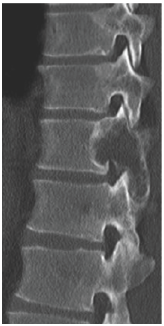

MSCT scan was performed to help in the diagnosis as showen in (Figure 4-7).

Figure 4:

Figure 5:

Figure 6:

Figure 7:

The usefulness of CT and MRI in planning the surgical management of destructive lesions of the spine and evaluating potential spinal instability is emphasized by the case presented.=